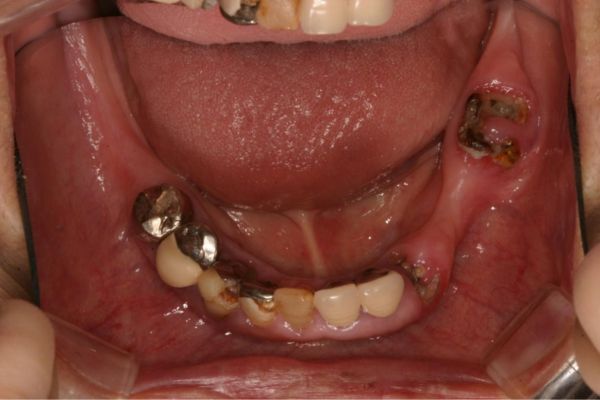

インプラント治療の症例紹介③

Before

After

主訴

むし歯の治療

治療内容

保存不可能な歯の抜歯

下顎にインプラント埋入し咬合再構成

治療費

2,688,400円(税込)

治療期間

14か月

治療回数

21回

想定されたリスク

※上部構造の形態が複雑になるため清掃が難しくなる。インプラント周囲炎の恐れがありました。

多数歯う蝕および多数歯欠損による咬合崩壊、保存不可能な歯の抜歯により上下無歯顎に。下顎に6本インプラント埋入する事で咬合再構成を行った。